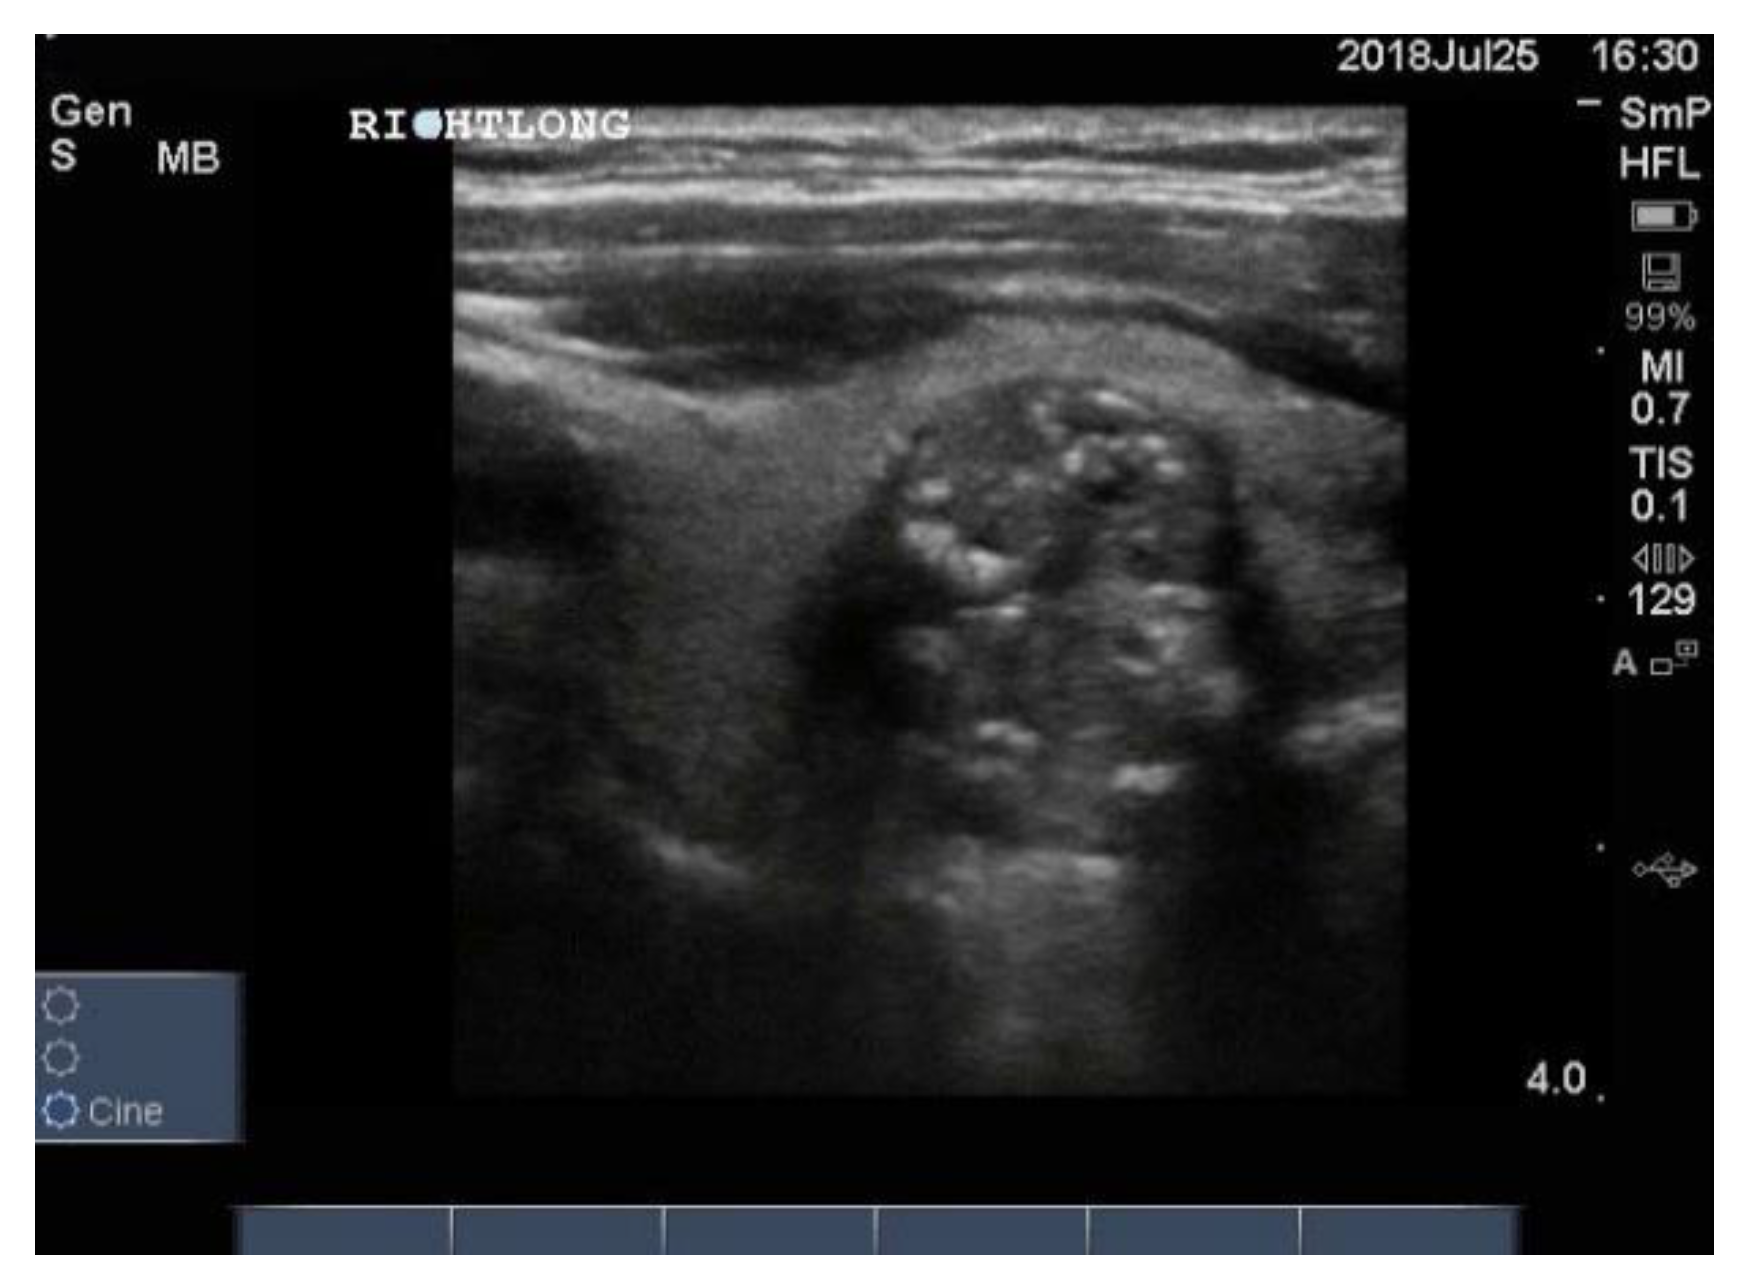

On follow up after treatment, usually total thyroidectomy followed by radioiodine, one looks for abnormal lymph nodes in the neck, indicating local relapse. In the case of papillary carcinoma, involved nodes are round, hypo echoic and may contain microcalcifications (Figure 14). They may have a cystic structure with posterior enhancement. It is recommended that the cervical lymph nodes be examined in all patients who undergo ultrasonography for whatever reason.

Figure 14.

Neck ultrasound of enlarged cervical lymph nodes from a patient with papillary thyroid cancer. The enlarged node is oval in shape, very hypoechoic and contains a few of the blotchy microcalcifications typical of papillary cancer. The arrow heads indicate the corners of the node. The little arrow inside referring to an echogenic focus.